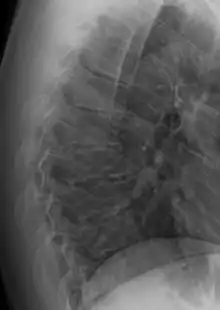

يعد داء شورمان داء عظمي غضروفي، ويعد أيضاً المرض الأكثر شيوعاً المسبب لفرط الحداب الهيكلي التقدمي للفقرات الصدرية أو الصدرية القطنية المصاحب لآلام الظهر خلال فترة سن المراهقة أو البلوغ.[1]

يعتبر الحداب الناشئ من مرض شورمان جامد أو صلب لا يتعدل مع انبساط أو انتصاب الظهر، وهذا عكس الحداب الصدري الوضعي حيث يتعدل مع انبساط الظهر ولا يعد مرضاً.[1]

عام 1964 م تم تعريف المرض على أنه توتد 5 درجات على الأقل من الجهة الأمامية للفقرة الواحدة، لثلاث فقرات صدرية متتابعة بحيث يكون ملاحظ على الصور الشعاعية.[2]

درجة الحداب يتم قياسها باستخدام طريقة زاوية كوب.